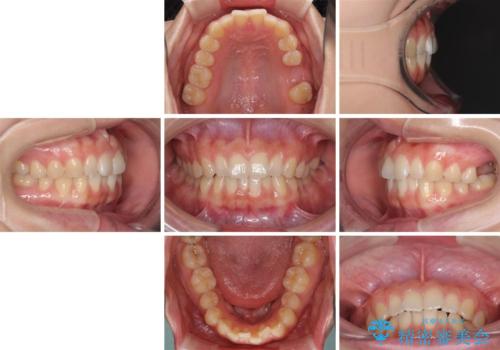

インプラントによる補綴治療とインビザライン矯正

- 抜歯が必要と診断された奥歯を気にして来院された患者様です。

抜歯の上インプラントによる補綴治療を行うこととなりましたが、前歯の叢生も気になるとのことで並行して矯正治療を行うこととしました。

歯列不正は軽微であったので、インビザラインによる矯正治療とし、矯正治療中にインプラント埋入を行う予定としました。

痛みがないので、ボロボロのまま放置していましたが、抜歯後は汚れが溜まりにくくなりスッキリとしたようです。

前歯のデコボコも解消され、ブラッシングが楽になりました。